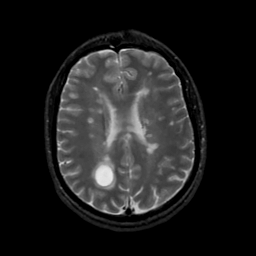

MR Study #20 October 6, 1991 -- Slice #32